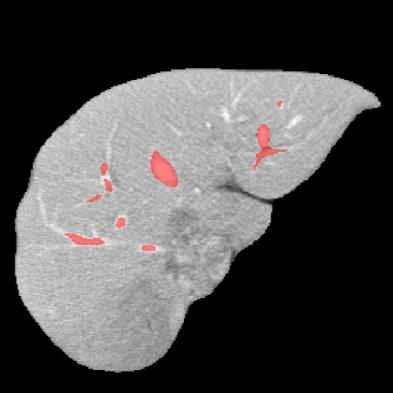

Manually segmenting the hepatic vessels from Computer Tomography (CT) is far more expertise-demanding and laborious than other structures due to the low-contrast and complex morphology of vessels, resulting in the extreme lack of high-quality labeled data. Without sufficient high-quality annotations, the usual data-driven learning-based approaches struggle with deficient training. On the other hand, directly introducing additional data with low-quality annotations may confuse the network, leading to undesirable performance degradation. To address this issue, we propose a novel mean-teacher-assisted confident learning framework to robustly exploit the noisy labeled data for the challenging hepatic vessel segmentation task. Specifically, with the adapted confident learning assisted by a third party, i.e., the weight-averaged teacher model, the noisy labels in the additional low-quality dataset can be transformed from "encumbrance" to "treasure" via progressive pixel-wise soft-correction, thus providing productive guidance. Extensive experiments using two public datasets demonstrate the superiority of the proposed framework as well as the effectiveness of each component.